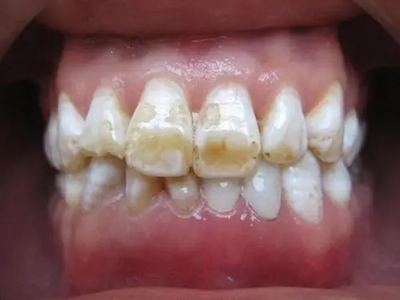

牙釉质发育不全牙表面上有坑图

牙釉质发育不全发展到严重时,导致牙釉质表面缺损,表现为带状、窝状的褐色凹坑,容易积存食物残渣诱发龋齿,表现为牙齿边上出现深褐色小洞。